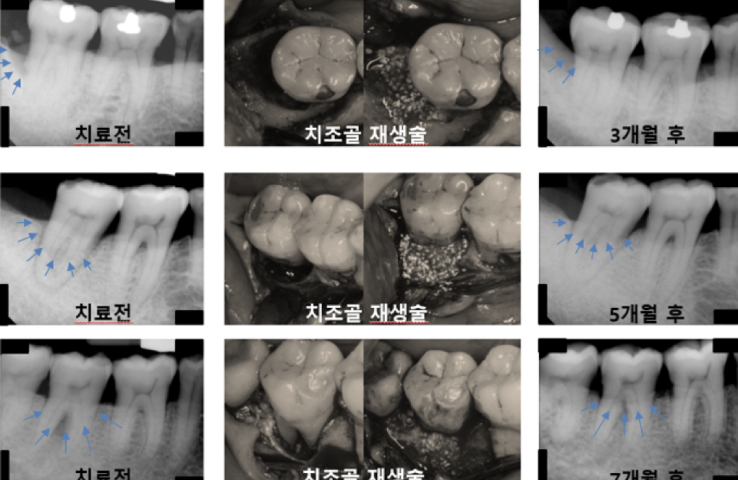

치조골 재생술

치아주변의 잇몸뼈가 심하게 녹은경우 치조골재생술을 통해 치아의 수명을 연장합니다.